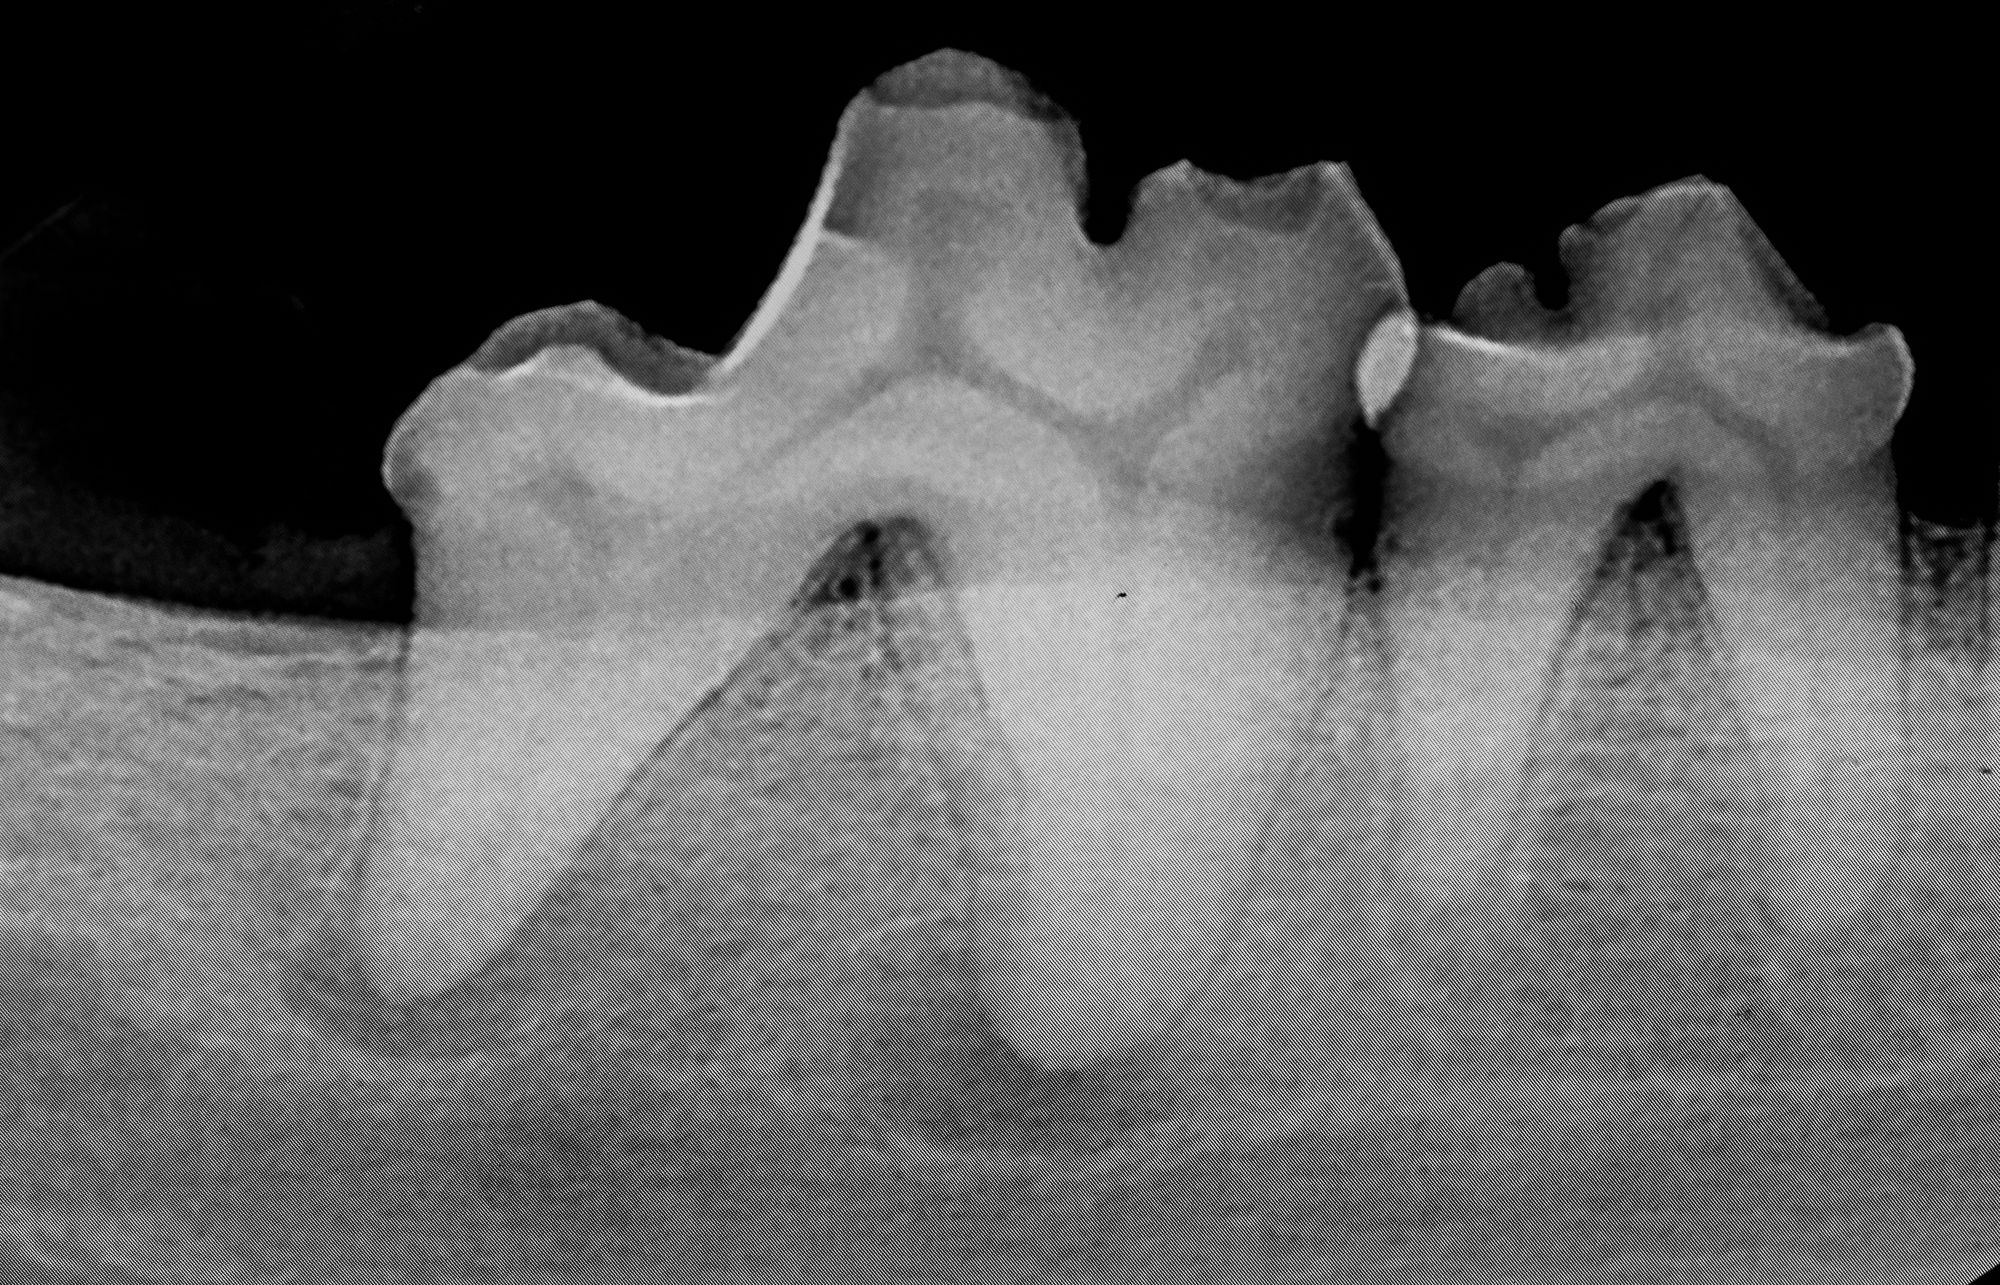

Although dental extractions are often routine, they can present unique challenges that increase the risk of this traumatic complication that every veterinarian fears.